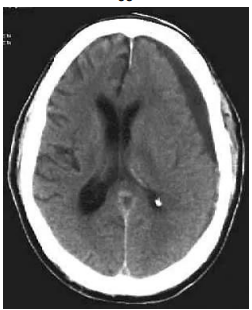

Senhor Liberato Tavares, 77 anos, comparece à emergência médica, trazido por filho. Evoluindo nas últimas semanas com letargia e confusão mental. Portador de hipertensão arterial sistêmica, hipotireoidismo e diabetes mellitus tipo 2, em uso regular de medicações e acompanhamento com clínico assistente. Há relato do filho de episódios prévios de tontura ao se levantar e TCE (traumatismo crânio encefálico) repetidos nos últimos meses, tendo último evento conhecido de ocorrência há 30 dias. Realizada tomografia em urgência abaixo:

FONTE: https://emedicine.medscape.com/article/247472-overview?form=fpf, acesso em: jun. 2024

Baseado na história clínica e na imagem: